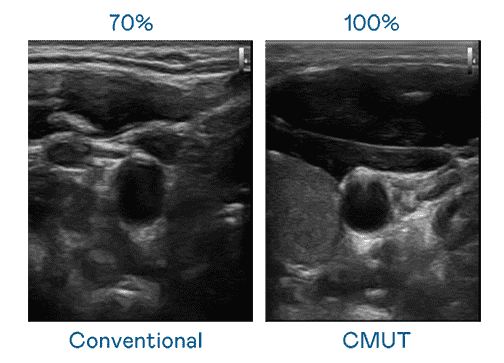

CMUT 技术是一种用电容式微机电元件来产生超音波讯号的技术。。。与传统 PZT 压电式技术相比,,,CMUT 频宽增加 30%,,,,更宽频的超音波讯号让影像解析度大幅提升,,,是实现高影像品质医疗超音波扫描、、促进精准医疗发展的关键技术。。

大频宽带来超清晰影像

超音波影像的解析度高低,,首先取决于探头能发出的讯号频宽。。。。尊龙集团 CMUT 可提供高清晰的超音波讯号,,提供高频宽、、、高灵敏度、、、、影像纹理细节更高的超音波影像,,协助医护人员缩短影像判读时间及利用精准的医疗影像进行诊断。。。